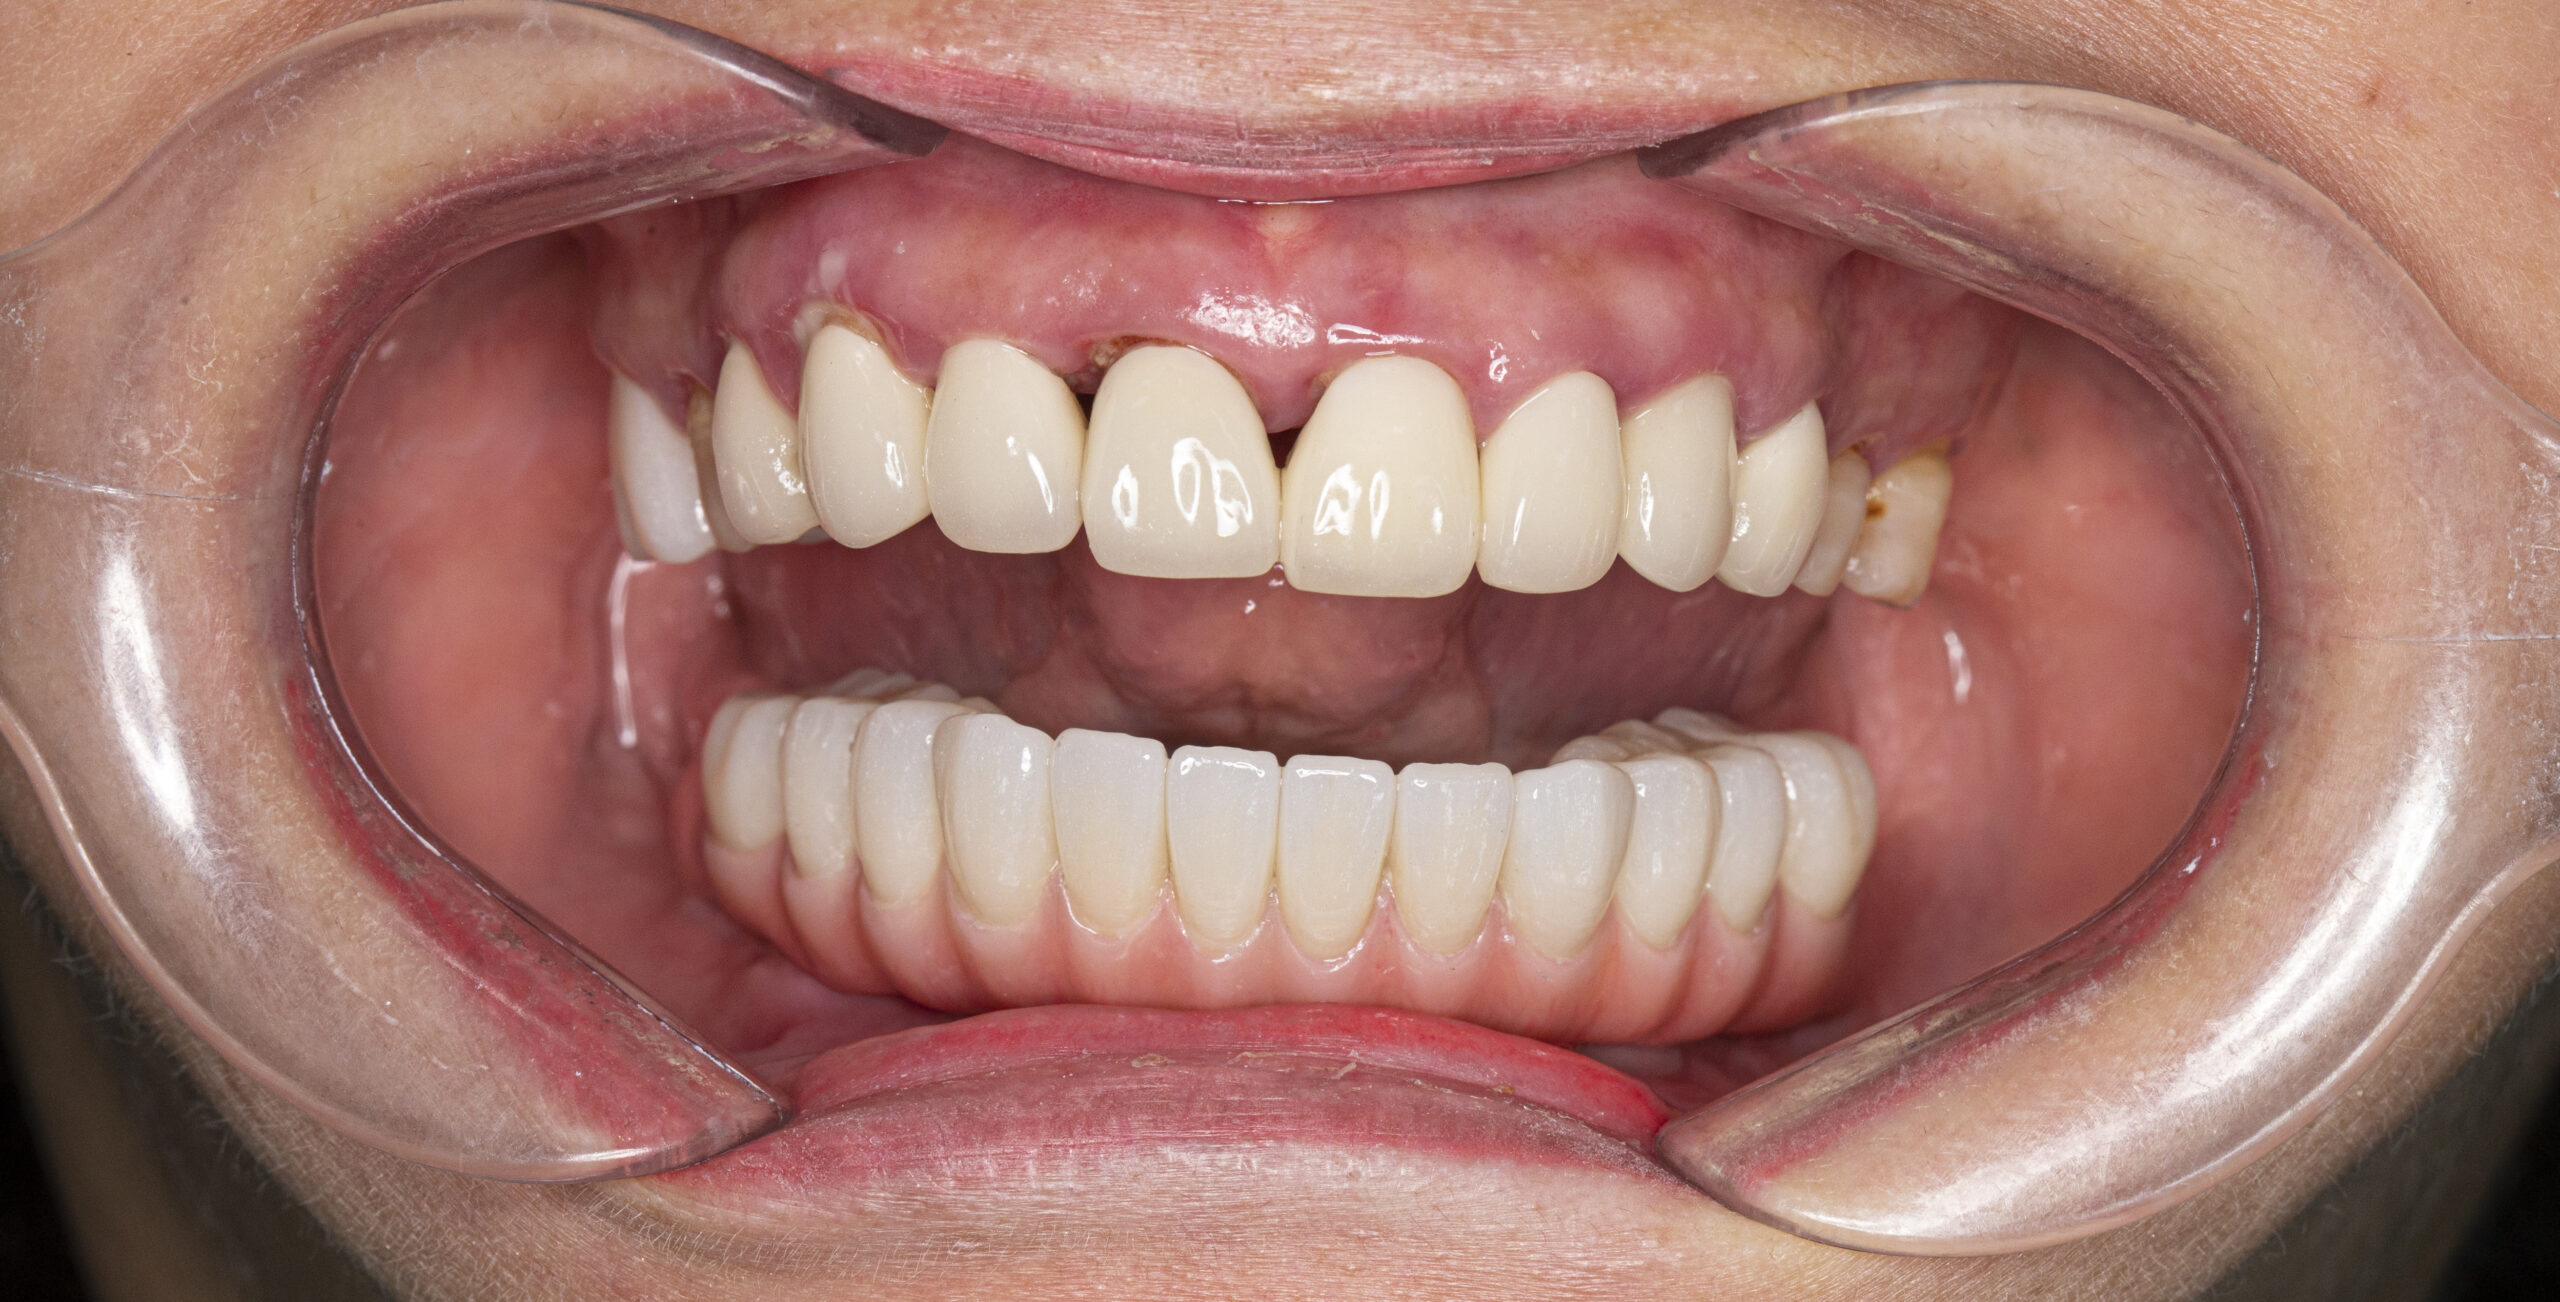

Bác Lã Quý Vĩnh (B18 Tập thể Kim Liên; 79 tuổi) trồng toàn hàm trụ Dentium 4 trụ và 1 hàm sứ nguyên khối 12 răng

Trường hợp mất răng của bác Lã Quý Vĩnh (B18 Tập thể Kim Liên; 79 tuổi); Trồng Implant toàn hàm dưới

Tình trạng:

Dùng hàm tháo lắp tạm thời hàm dưới, còn vài chân răng không ăn uống được

Kế hoạch điều trị:

+ Nhổ các các chân răng còn sót lại

+ Trồng răng toàn hàm dưới 4 trụ Dentium của Hàn: 12 Triệu x 4 = 48 Triệu

+ Làm hàm sứ nguyên khối Zirconia 12 răng: 48 Triệu

Tổng chi phí điều trị trồng răng toàn hàm trên: 48 Triệu + 48 triệu = 96 Triệu